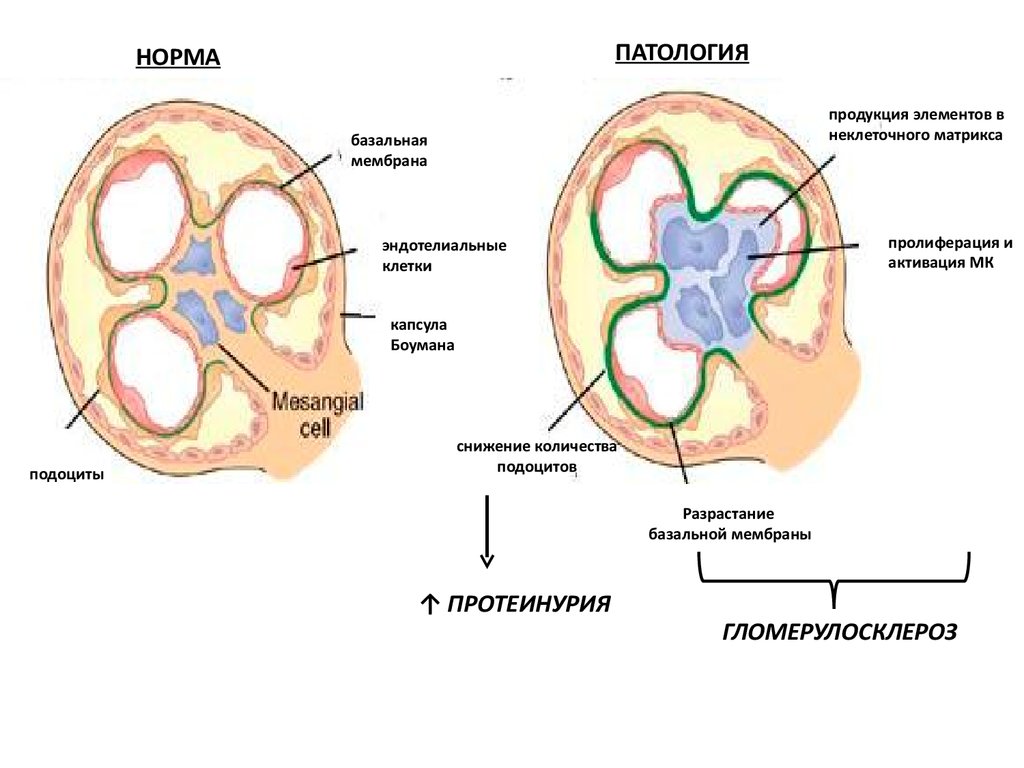

Механизм остро го диффузного гломерулонефрита